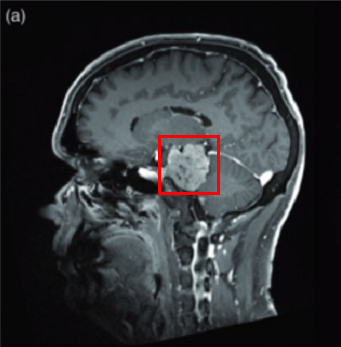

法国巴黎一位53岁男士,因三叉神经痛合并三叉神经感觉减退,在当地神经外科医院医院,查出左侧较大岩斜脑膜瘤(27立方厘米)。脑磁共振(mri)显示从幕部可见明显的轴外肿瘤,岩斜向外扩张,对脑干有明显的挤压效应。经该院神经外科教授兼主席Sebastien Froelich教授主刀手术后,这个复杂位置的脑膜瘤得以完整切除,无神经功能损伤及相关的并发症。

对此,负责主治的Sebastien Froelich教授,同其手术团队联合咨询后,为患者确定了具有针对性的手术方案--术前需进行血管造影并栓塞,以确定主要动脉供血者,促进手术切除及降低手术风险,再行手术切除。

图示:通过这例手术对比术前术后影像对比,可见术后切除率达到了近乎全切。而患者术后并没有明显得神经损伤症状。